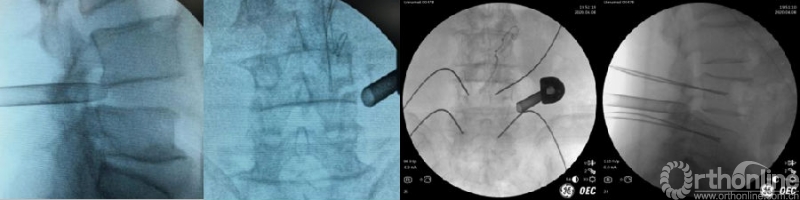

(5)穿刺及导丝置入

无菌消毒,铺无菌巾、单后,根据术前规划及椎弓根体表投影点置入穿刺针,C臂正侧位透视确认穿刺针位置满意。置入导丝,深度进入椎体后缘达椎体中心位置,避免过浅,以免操作过程中导丝滑落。如果先进行减压和融合的话,穿刺针需平行椎间隙置入。

(6)逐层切开及通道放置

沿穿刺针插入导丝,纵行切开皮肤长约1.5cm,逐级扩张皮下、腰背筋膜至关节突关节,放入半齿工作套管或U型工作套管等,C臂再次透视套管位置位于上关节突腹侧,尖端尽力到达椎间盘表面。如果是先置入4枚经皮螺钉导丝的话,则需选择尾侧一枚经皮螺钉切口,适当向头端延长约1.5cm后,平行椎间隙置入工作套管。

(7)钝性剥离软组织,置入U-T工作套管

沿穿刺针全层注入肾上腺素混合液,尤其在关节突关节周围;第一级圆锥形导杆需要平行椎间隙置入到上关节突腹侧,适度进入椎间孔到达椎间盘表面,避免向头侧挤压到出口根;逐级扩张套管,沿导杆停留在关节突骨性表面并向四周钝性剥离软组织;置入U型工作套管,其间断适度插入到上关节突腹侧;连接内镜主机及冷光源,两路三升袋盐水同时灌注,打开射频刀头调整至安全强度。置入T型工作套管,镜下清理关节突关节软组织并充分止血,对视野内所有结构的预止血至关重要。